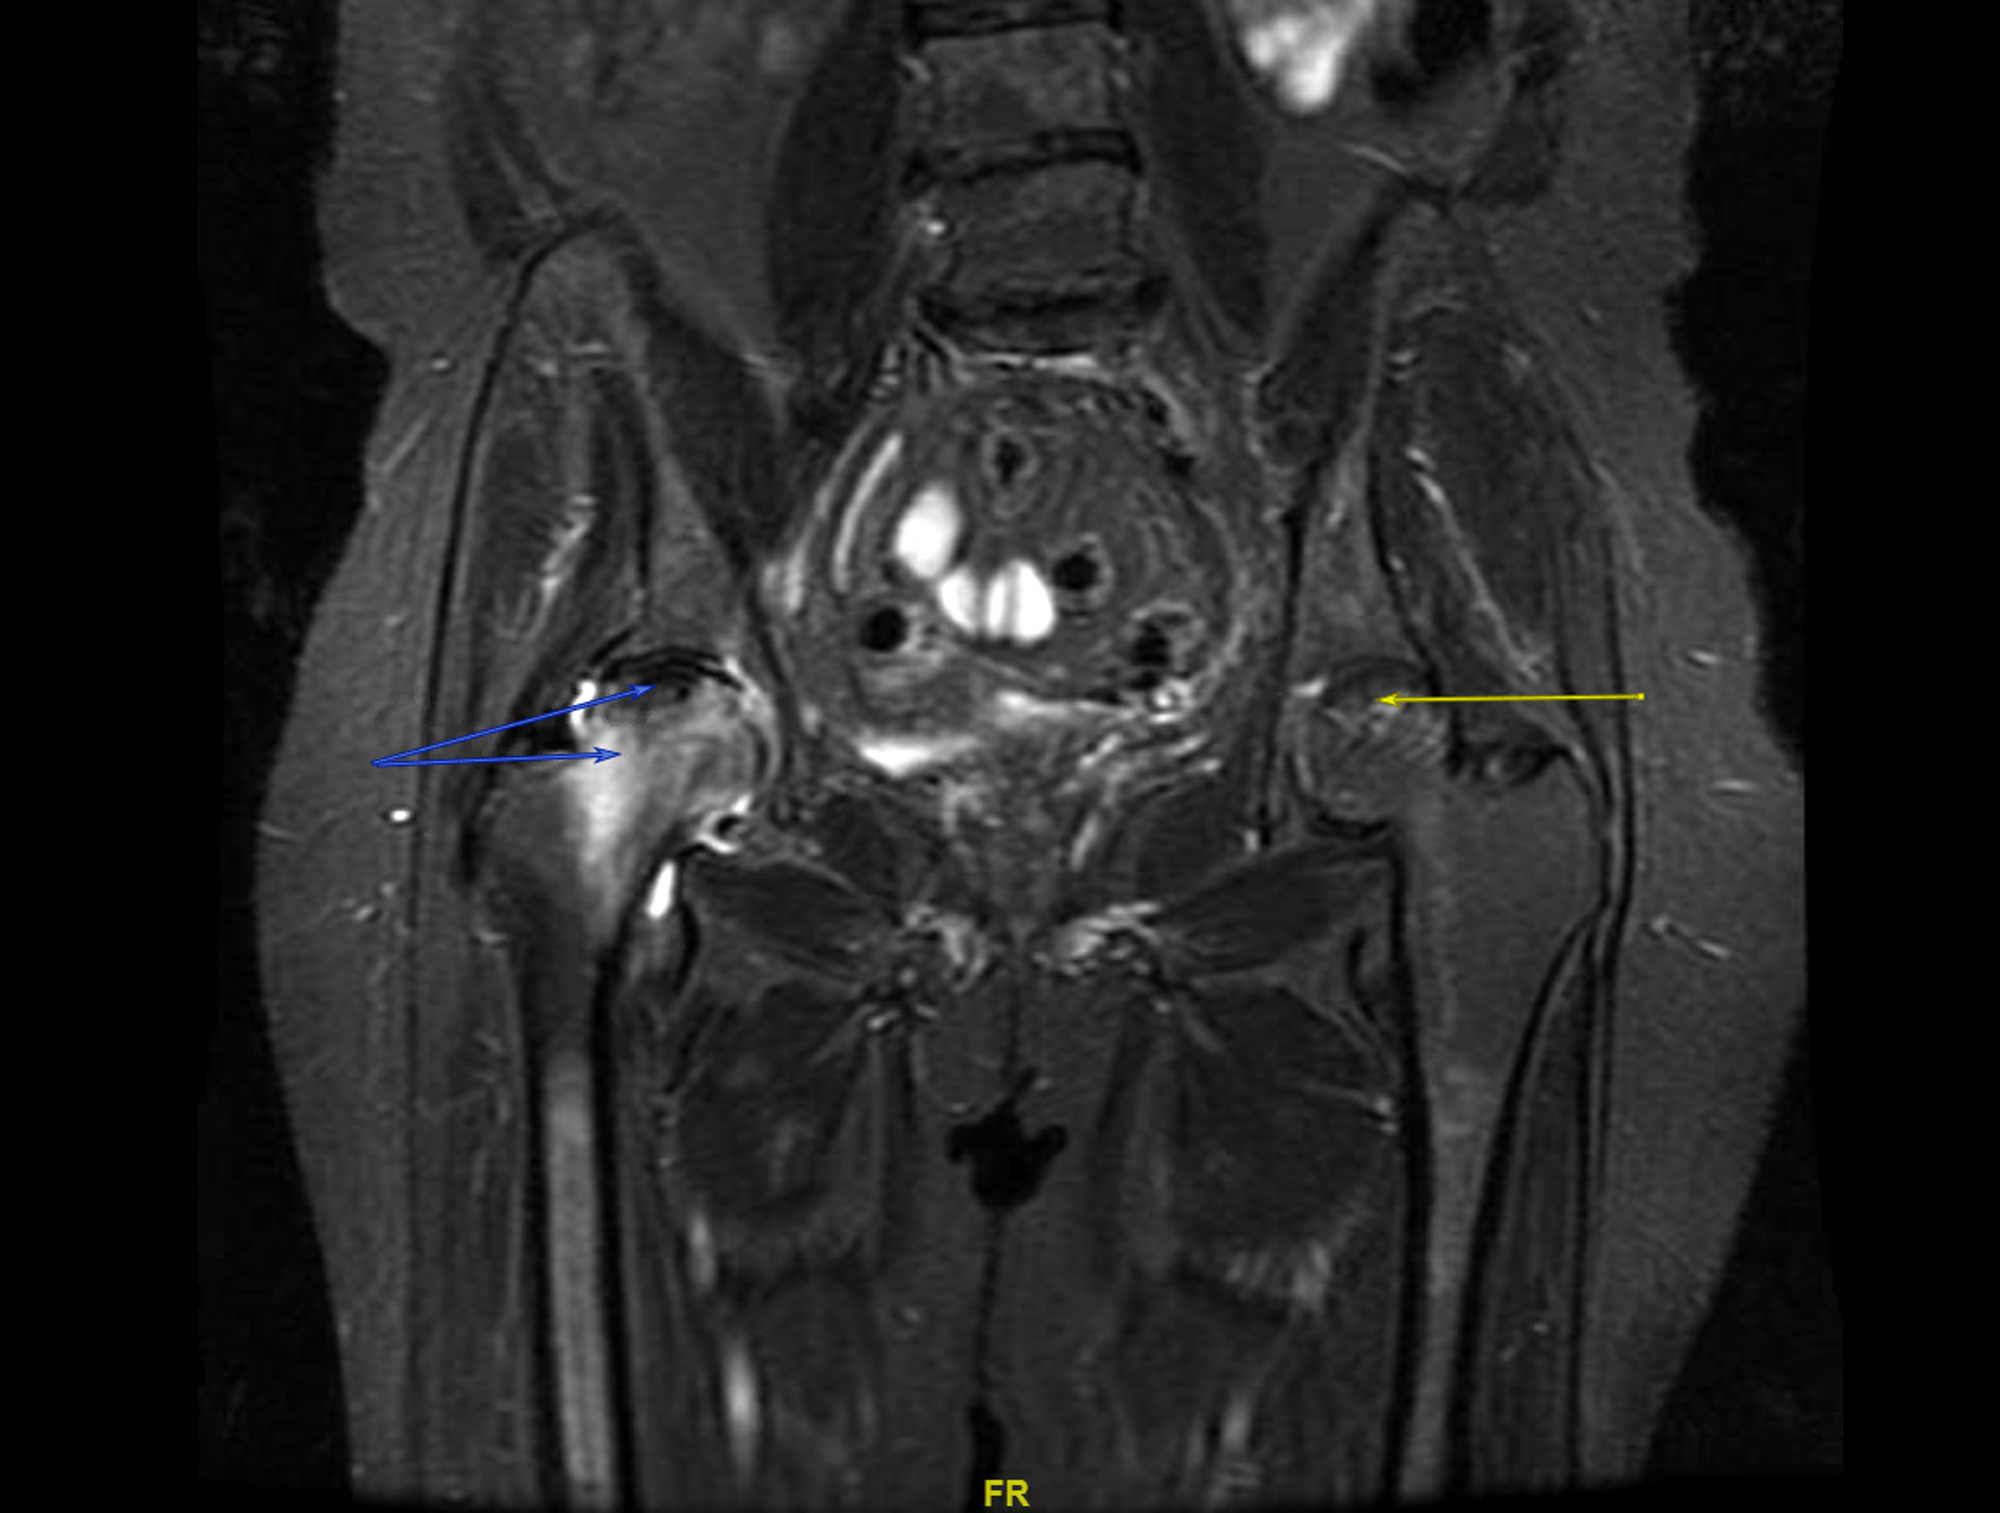

MRI PELVIS

MRI PELVIS Hip Vs Lumbar Mri Lumbar mri will show from the lower thoracic spine (t10 or so) down to. To answer your question, no. A thorough patient history is crucial to differentiate hip pathology from lumbar spine pathology. a lumbar mri specifically examines the lumbar section of your spine — the region where back problems commonly originate. A thorough patient history begins. how. Hip Vs Lumbar Mri.